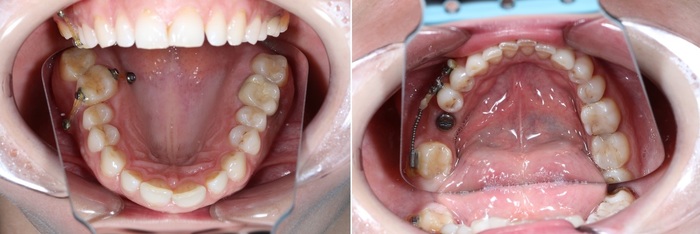

Для этого чаще всего используются ортодонтические минивинты. Для начала необходимо удалить зуб мудрости, потому как он будет только мешать (про зубы мудрости у меня есть целый ряд статей). Далее установить минивинт:

Вот эта белая палка справа – это и есть винт. Специфика этих винтов в том, что они не срастаются с костной тканью, а тупо вкручиваются в кость и держатся за счёт своей резьбы. Это позволяет без проблем и анестезии (!) выкрутить этот винт после окончания передвижения зуба.

Так вот: ортодонт дал тягу к винту при помощи специальных резинок. Далее пациентке необходимо будет посещать ортодонта 1-2 раза в месяц для замены тяг. Обычно такое передвижение занимает в среднем три месяца.

Так как зуб встал на своё место, резиновые тяги были заменены на металлические лигатуры для того, чтобы просто зафиксировать положение зуба. Это вот те белые полоски, тянущиеся от зуба к винту.

Обратите внимание: необязательно устанавливать полноценную брекет-систему для того, чтобы устранить эту проблему. Достаточно приклеить 3 брекета на 4-й, 5-й и 7-ой зубы. Затем при помощи специальной пружины толкать проблемный зуб на свое место. На верхней челюсти ситуация несколько иная. Для устранения проблемы устанавливаются два ортодонтических винта: один со стороны щеки, а второй со стороны неба. К зубам клеятся две кнопки, и дается тяга.

И под другим углом: